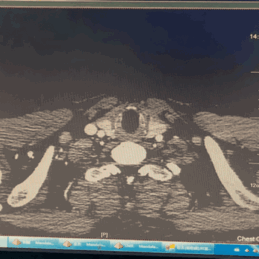

术前CTA详解:

主动脉弓穿透性溃疡,病变大小分别约11*11mm、5*9mm;左颈总动脉后缘处主动脉直径32mm,左锁骨下动脉前缘处主动脉直径29mm,左颈总动脉后缘距离左锁骨下动脉前缘8mm,左颈总动脉后缘距离穿透性溃疡近端7mm。